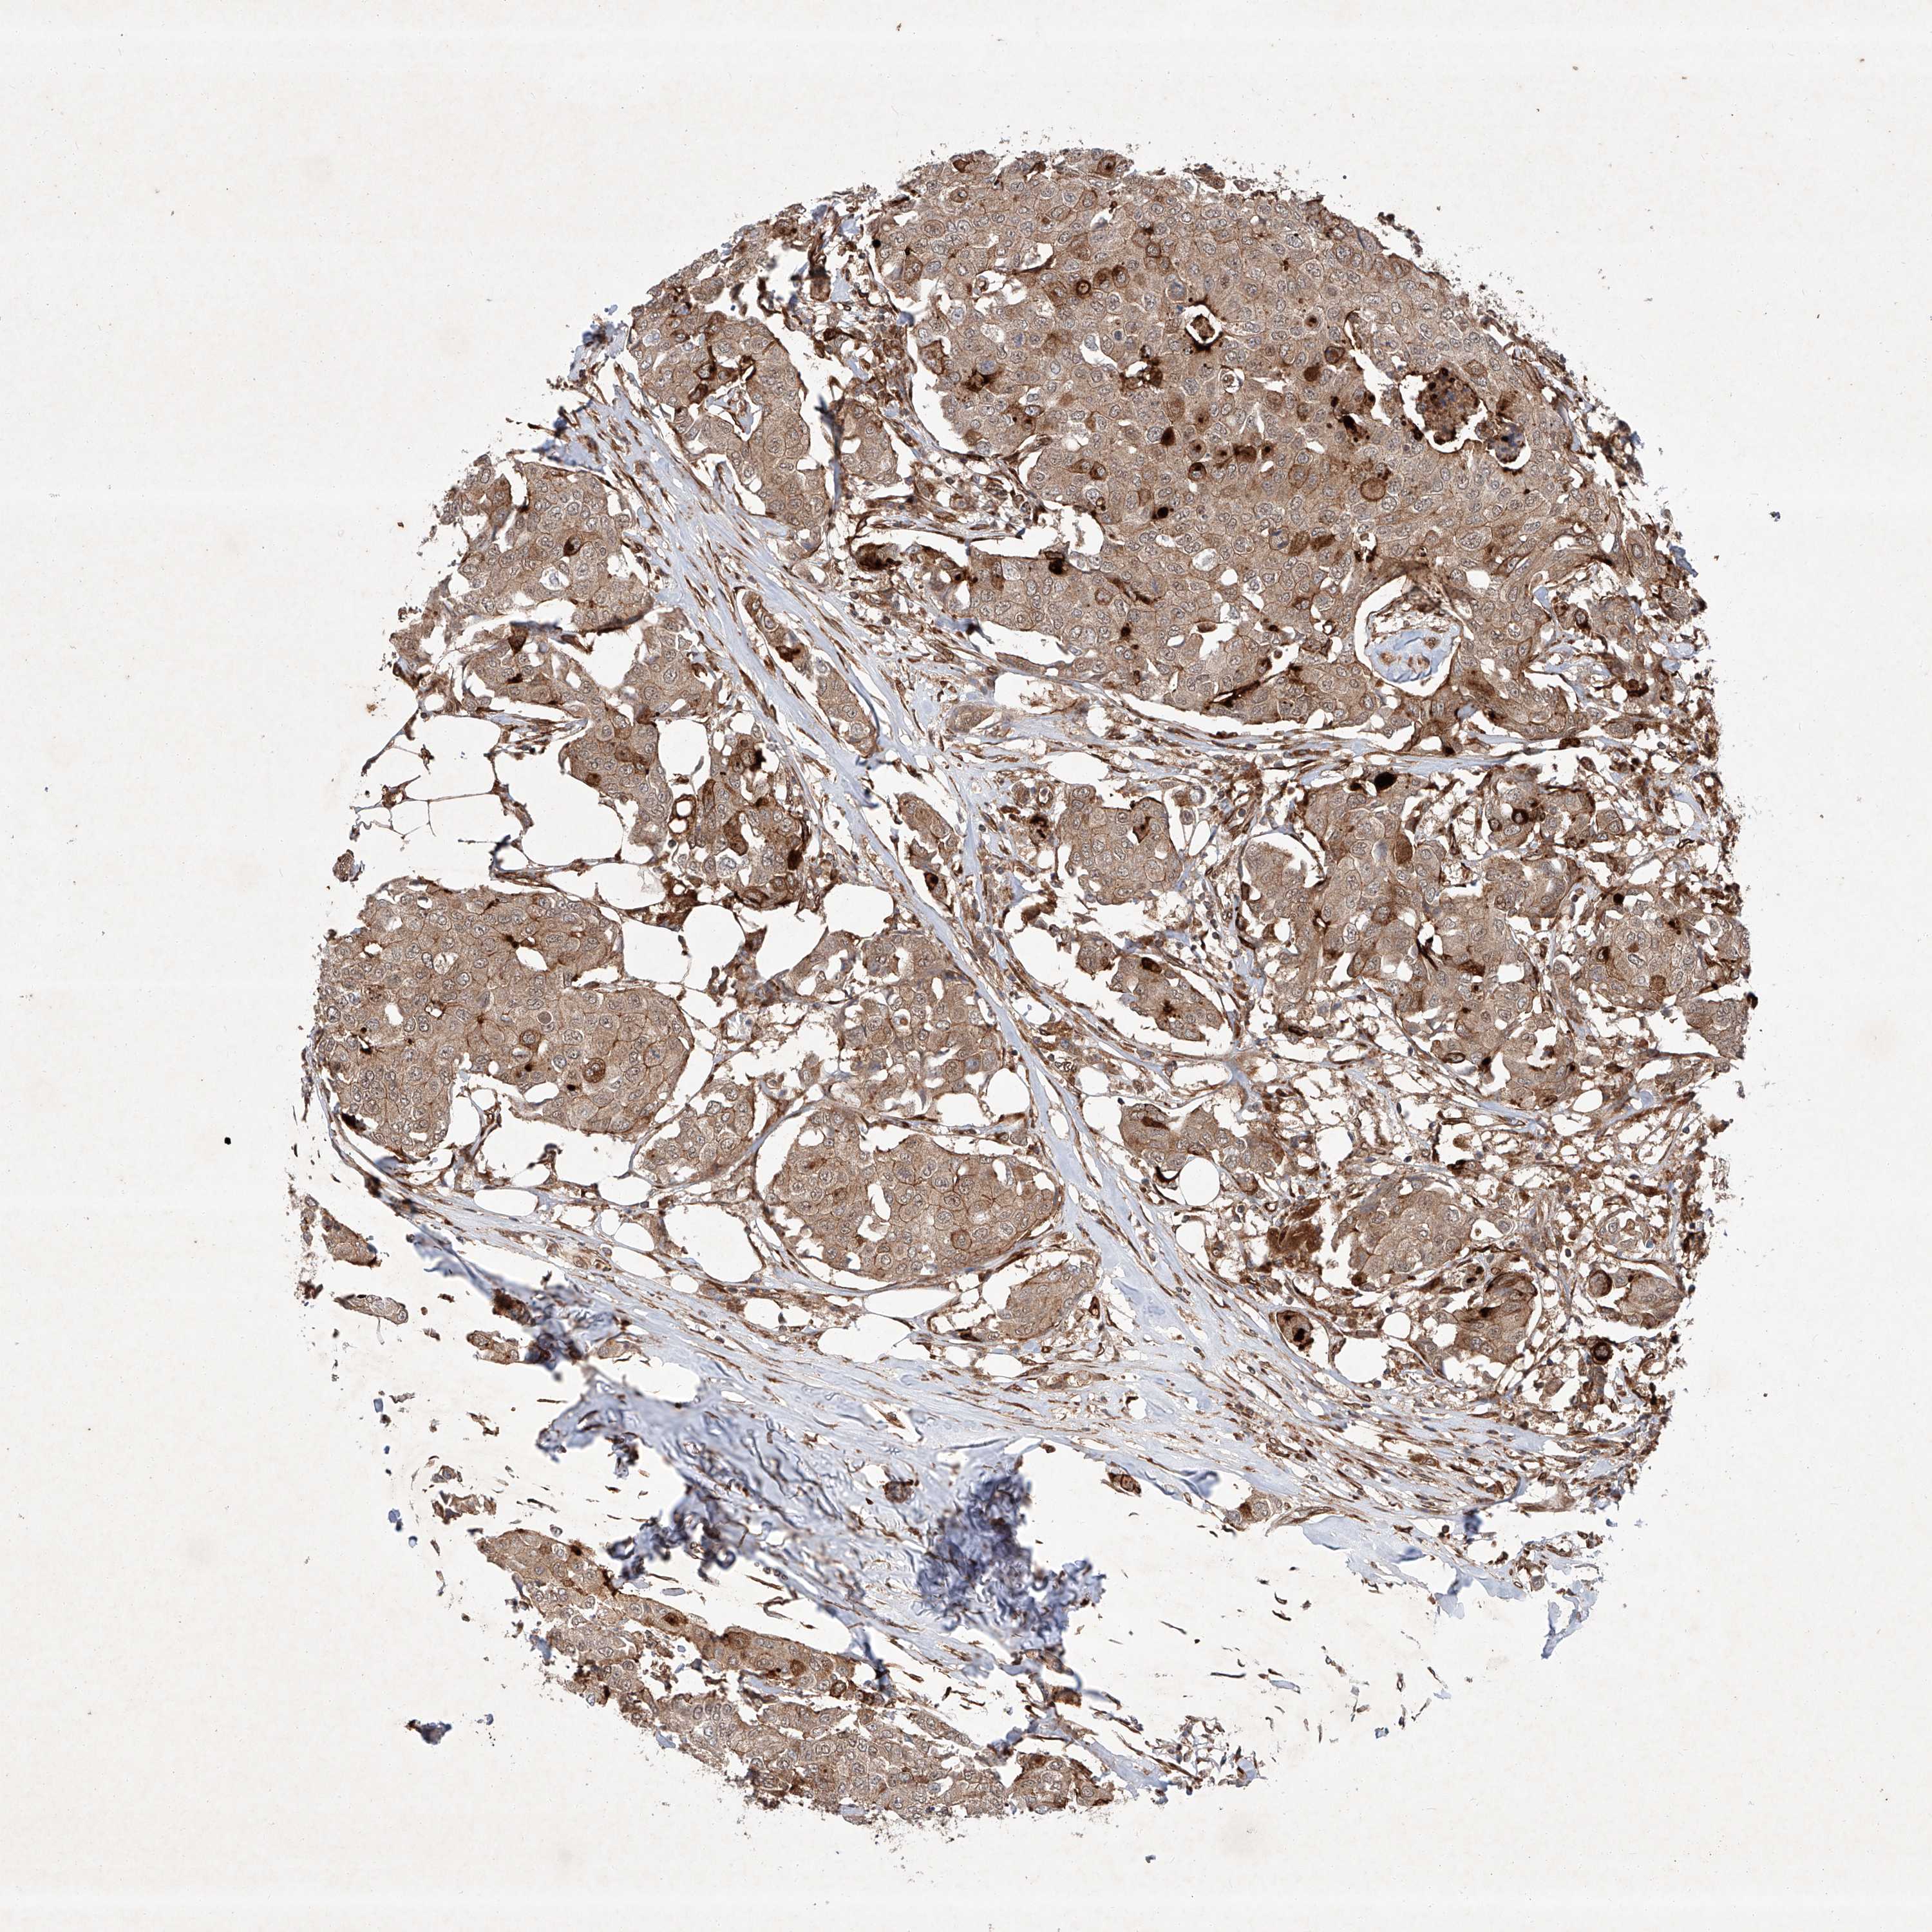

CANCER BREAST CANCER Show tissue menu

BRCA TCGA BRCA VALIDATION PROTEIN EXPRESSION

Breast cancer

Human cancer

Breast invasive carcinoma